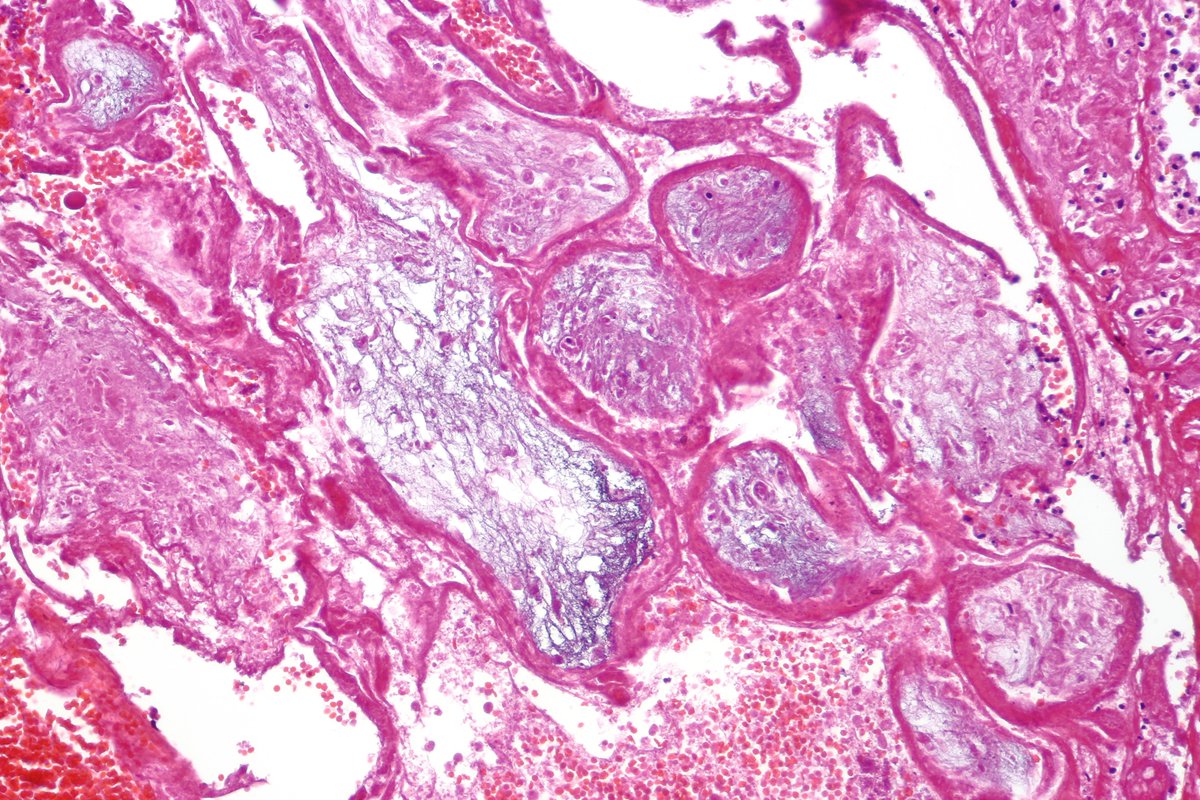

Pancreatobiliary-type adenocarcinoma lymph node metastasis showing well-formed, irregular glands associated with desmoplastic stroma. #pathology #GIPath